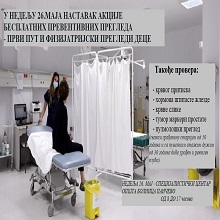

У оквиру редовне превентивне акције Министарства здравља Републике Србије, и ове недеље смо у специјалистичком центру Опште болнице Панчево организовали акцију превентивних прегледа која је омогићила нашим грађанима да провере своје здравље и тиме значајно утичу на превенцију даљем развоју болести, такође пацијенти који су желели могли су се вакцинисати против сезонског грипа. |

И ове недеље организујемо акцију превентивних прегледа. Позивамо грађане да дођу у специјалистички центар Опште болнице Панчево, у недељу, 6. октобра од 8 до 17 часова и провере своје здравствено стање. Прегледе могу обавити сви грађани Панчева и околине, без здравствене књижице. Акције које спроводи Министарство здравља за циљ имају рану дијагностику и промоцију превенције као најефикаснијег начина бриге о здрављу. |

И овог викенда, у оквиру акције Министарства здравља, у Панчеву су одржани бесплатни превентивни прегледи. Сви грађани, укључујући и оне без здравственог осигурања, имали су прилику да провере своје здравствено стање. |

у недељу 15. септембра 2024. године, у периоду од 08:00 до 17 часова, одржаће се превентивни прегледи у здравственим установама целе земље, као и у Општој болници Панчево. |

Акција превентивних здравствених прегледа у Панчеву

Још једна у низу акција превентивних прегледа у организацији Министарства Здравља Републике Србије одржаће се у Општој болници Панчево, 8. септембра 2024. године од 08 до 17 часова. |

Без заказивања и здравствене књижице и ове недеље грађани Панчева могли су да преконтролишу своје здравље. Превентивни прегледи битни јер се у већини случајева болест открије на време и може да се излечи и контролише на адекватан начин. |

Акцијом бесплатних превентивних прегледа, које спроводи Министарство здравља, 14. јула 2024.године у периоду од 8.00 до 17.00 часова у специјалистичком центру Опште болнице Панчево организујемо превентивне прегледе. Сви наши грађани, и они без здравственог осигурања, биће у прилици да без заказивања и упута, брзо и ефикасно провере своје здравствено стање |

| У склопу акције превентивних прегледа које је организовало Министарство здравља и ове недеље прикључили су се Општа болница Панчево и Дом здравља. Наши најмлађи суграђани такође ове недеље могли су да се јаве педијатру, јер су прегледи били организовани и за њих. |

| После изузетног одзива током претходне акције када је у Србији прегледано око 23.000 грађана, Министарство здравља организовало је поново превентивне прегледе са циљем да се у раној фази болест дијагностикује, а тиме и да степен излечења буде већи. Грађани су у панчевачкој Општој болници и Дому здравља, као и у осталим здравственим установама широм Србије могли без упута, заказивања и здравственог осигурања да обаве основне лабораторијске анализе, измере крвни притисак, провере хормоне штитне жлезде и ураде тумор маркере простате. |

Услед великог интересовања грађана, Министарство здравља у недељу, 26.маја, наставља акцију бесплатних превентивних прегледа, коју спроводи у циљу ране дијагностике и промоције превенције. |

Грађани нису крили задовољсто што су на једноставан начин могли да провере своје здравље. Министарство здравља наставило акцију превентивних прегледа са циљем да се у раној фази болест дијагностикује. Грађани како у целој Србији тако у Општој болници Панчево су могли без упута, заказивања и здравственог осигурања уз преглед наших лекара измере крвни притисак, вредност шећера у крви, ураде ЕКГ и ултразвучни преглед абдомена. |

Акција бесплатних превентивних прегледа, које спроводи Министарство здравља у циљу ране дијагностике и промоције превенције као најефикаснијег начина бриге о здрављу, биће настављена у недељу, 19. маја од 8 до 17 часова, у специјалистичком центру Опште болнице Панчево. |